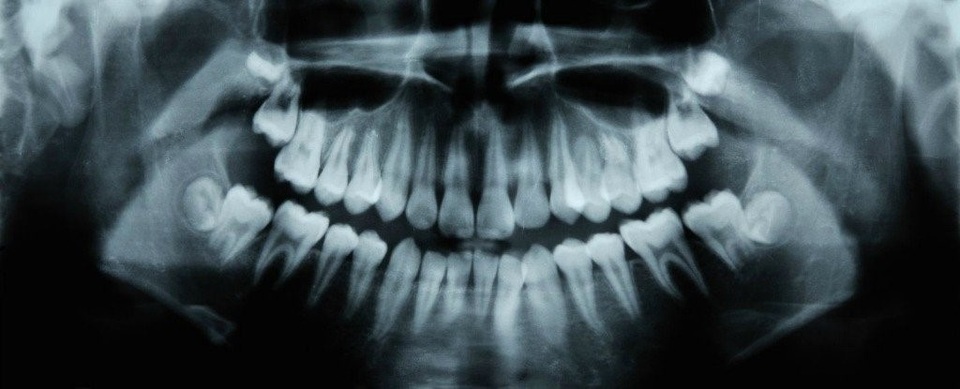

Hàn răng có lẽ sẽ sớm bị bỏ lại trong đống tro tàn của lịch sử, nhờ một khám phá gần đây về một loại thuốc tên Tideglusib. Được sáng chế và thử nghiệm để điều trị bệnh Alzheimer, năm ngoái các nhà khoa học phát hiện ra rằng loại thuốc này cũng tình cờ giúp thúc đẩy cơ chế mọc lại răng tự nhiên ở chuột, cho phép răng chữa trị sâu răng.

Tideglusib hoạt động nhờ việc kích thích các tế bào gốc trong tủy răng, nguồn ngà răng mới. Ngà răng là chất được khoáng hóa bên dưới men răng bị ăn mòn bởi sâu răng.

Răng có thể tự tái sản sinh ngà răng mà không cần hỗ trợ, nhưng chỉ trong những điều kiện nhất định. Tủy răng phải được lộ ra qua nhiễm trùng (như sâu răng) hay chấn thương để thúc đẩy sự sản sinh ngà răng. Nhưng kể cả như vậy, răng chỉ có thể mọc lại một lớp rất mỏng – không đủ để chữa các lỗ sâu răng, thường khá sâu. Tideglusib làm thay đổi kết quả này vì nó sẽ ngừng việc sản sinh enzyme GSK-3, ngăn chặn sự hình thành ngà răng.

Trong nghiên cứu năm 2017, nhóm nghiên cứu đã chèn các miếng bọt biển nhỏ, có thể phân hủy sinh học làm từ collagen ngâm trong Tideglusib vào các lỗ răng sâu. Những miếng bọt biển này khiến ngà răng phát triển và trong vòng sáu tuần, vết răng sâu đã được chữa khỏi. Cấu tạo collagen của bọt biển đã tan chảy, chỉ để lại chiếc răng nguyên vẹn.